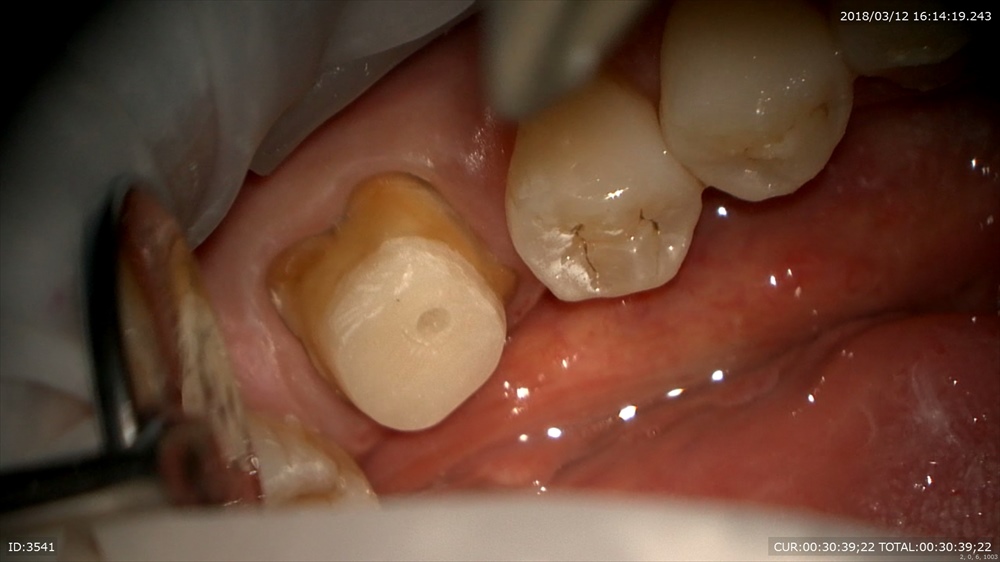

本日根管充填

この方は根管治療が終わり土台をつけ仮歯を作成しました。

この方も根管治療は2回。

根管治療後も精密な土台と仮歯を作り細菌感染を防ぎます。

土台

仮歯を